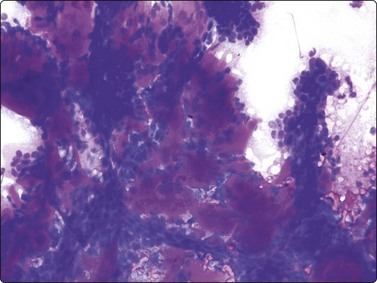

Fat necrosis (Fig. 7.19)

image image image

Fig. 7.19 Fat necrosis

(A) Postoperative fat necrosis. Necrotic tissue, debris and macrophages; fragment of adipose tissue upper right (MGG IP); (B) Fragments consisting of altered adipocytes, macrophages and fat droplets (MGG, IP); (C) Several multinucleated histiocytes with foamy cytoplasm (MGG, HP).

Criteria for diagnosis

A ‘dirty’ background of granular debris, fat droplets and fragments of adipose tissue,

Foamy macrophages, multinucleated giant cells and adipocytes with bubbly cytoplasm,

Chronic inflammatory cells,

Absence of epithelial cells.

Postoperative changes in response to prior surgical excision or biopsy give similar findings. Fat necrosis is always in the differential diagnosis of nodules in scars or chest wall after surgery, particularly mastectomy. Vigorous or repeated palpation of breast tissue or previous aspiration of the site can result in the same changes. The aspirate is usually scanty, sometimes of oily fluid, and consists mainly of fat with some foamy macrophages or altered, vacuolated adipocytes and multinucleated histiocytic giant cells. The untidy background of granular debris represents the actual necrosis and is the most specific diagnostic feature (Fig. 7.19A,B).

Problems in diagnosis

Lipid cysts,

Macrophages mistaken for atypical epithelial cells,

Carcinoma cells with a macrophage-like appearance.

The dissolution of fat leads to a lipid cyst. Lipid cysts can be recognised by radiologists. The liquid is very viscous and may be yellow, clear, or have an unusual appearance of a gray-white color possibly corresponding to saponification. Solidification of the fluid in the test tube occurs after aspiration. The material does not stain with MGG although it may not dissolve completely during staining. A crystalline appearance is sometimes present in unstained slides.

The dispersed presentation of macrophages, particularly if the cytoplasm is dense or nonvacuolated and the nuclei are large with an irregular shape and prominent nucleoli, may mimic a malignant cell pattern, particularly in air-dried MGG smears. Multinucleate forms and foamy cells with similar morphology are helpful in preventing error (Fig. 7.19C).102 Conversely, some carcinoma cells may resemble macrophages. Immunostaining or excision is sometimes necessary.